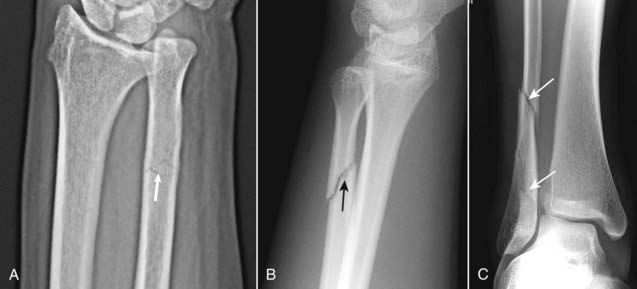

Figure 22-6 Segmental fracture and butterfly fractures.

These are two comminuted fractures. A, This is a segmental fracture in which a portion of the shaft exists as an isolated fragment. Notice how the fibula has a center segment (S) and two additional fragments, one on either side (solid white arrows). B, A butterfly fragment is a comminuted fracture in which the central fragment has a triangular shape (dotted white arrow).

Figure 22-7 Transverse, diagonal, and spiral fracture lines.

A, In a transverse fracture (solid white arrow), the fracture line is perpendicular to the long axis of the bone. B, Diagonal or oblique fractures (solid black arrow) are diagonal in orientation relative to the normal axis of the bone. C, Spiral fractures (solid white arrows) are usually caused by twisting or torque injuries.